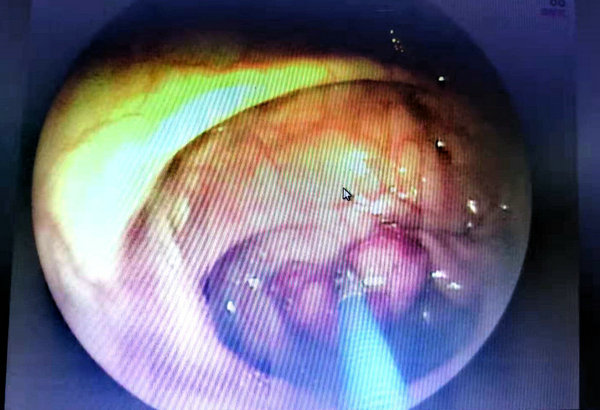

53岁的李先生因间断腹痛1个多月,最近1天突然腹痛加重,无法正常生活,于是在家人陪同下急诊入院,经消化道造影、纤维结肠镜检查发现,距肛门约60厘米处有一隆起病变,边界不清楚,表面污秽肠腔明显狭窄;距肛门30厘米处发现一个大小约2.0X1.0厘米息肉,表面分叶、糜烂。